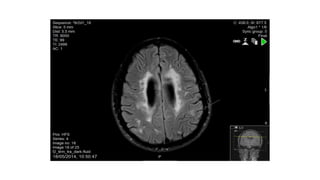

T1 lesions with gadolinium enhancement

T1 lesions withgadolinium enhancement